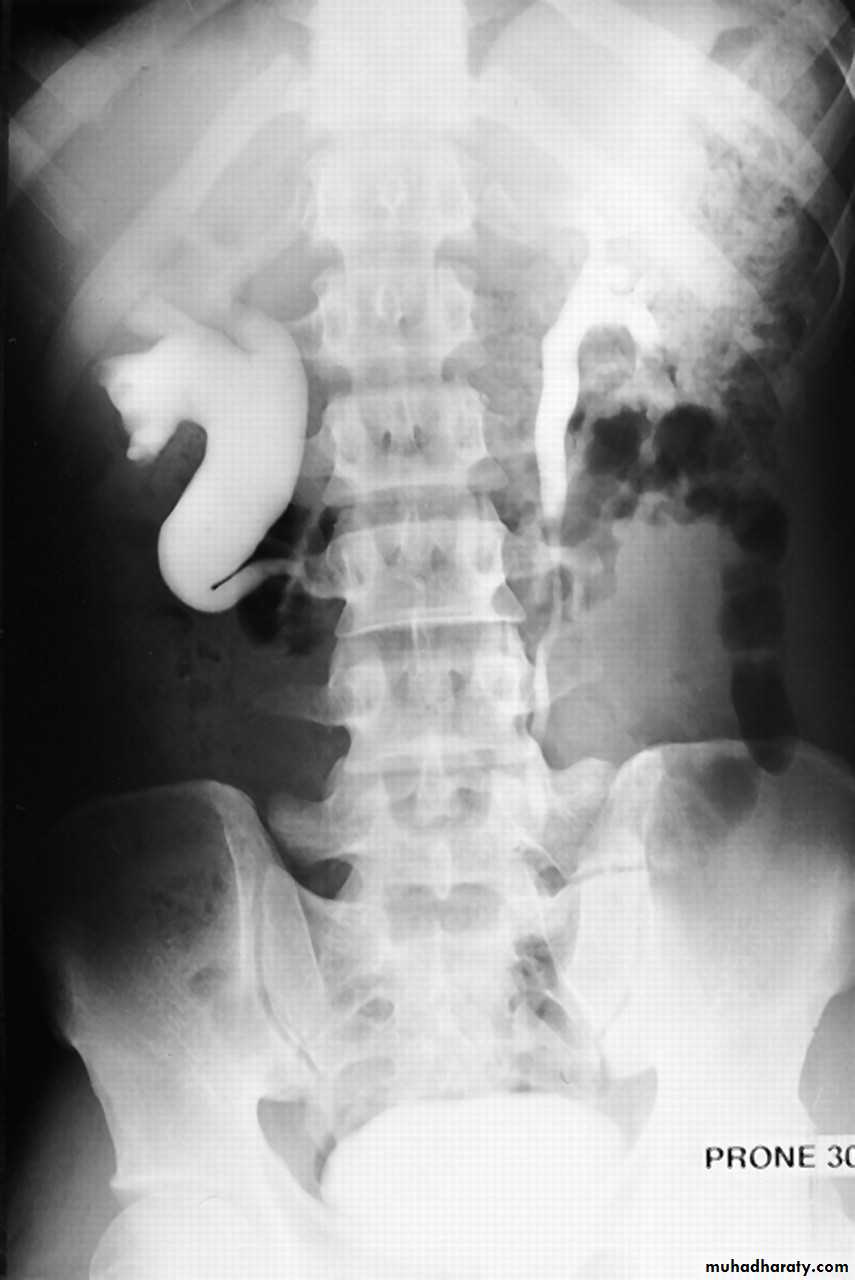

IVU

Large kidney .

Lobulated out-line.

Distortion of pelvi- calyceal system depend on cyst size, number and position.

In advanced cases there is elongation and stretching of minor and major calyces ( spider leg).

In advanced cases IVU shows non-functioning kidney .